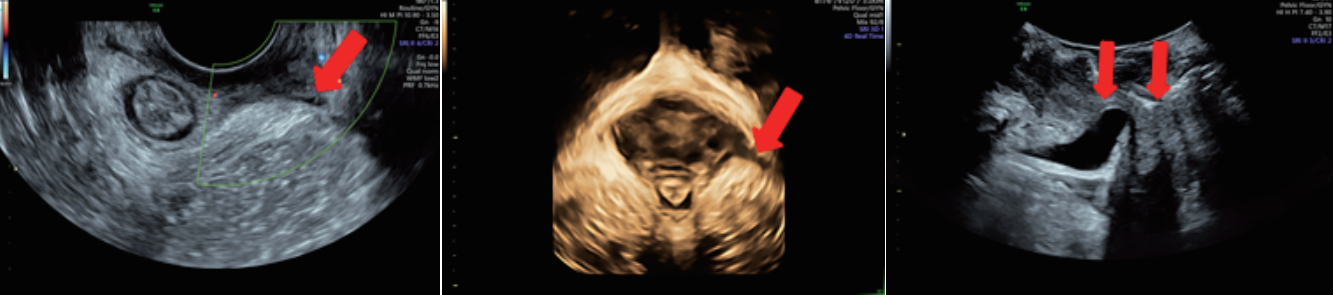

廣泛應(yīng)用于婦產(chǎn)超聲臨床領(lǐng)域,尤其在產(chǎn)科、不孕不育生殖醫(yī)學(xué)和女性盆底功能障礙性疾病等領(lǐng)域,提供高品質(zhì)圖像及專(zhuān)業(yè)的婦產(chǎn)超聲臨床解決方案。

案例圖

女性產(chǎn)后盆底功能檢查

輸卵管